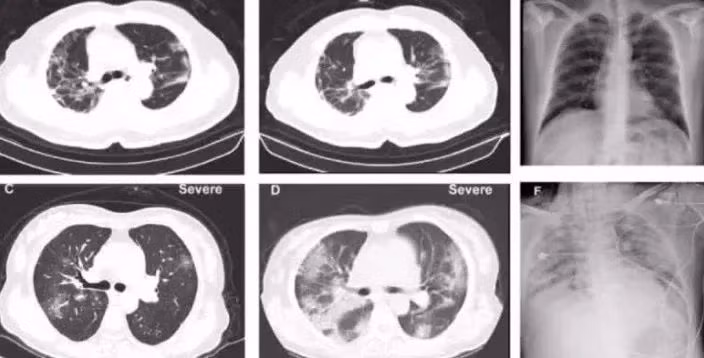

![]() |

| Hình chụp CT phổi của bệnh nhân nhiễm coronavirus. |